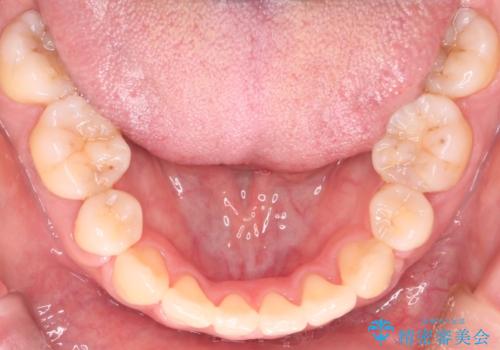

- 上の前歯のデコボコが気になるということで来院されました。

叢生量(デコボコ)が多いため、上下左右4番目の歯を抜歯してワイヤー矯正を行う治療計画を立てました。